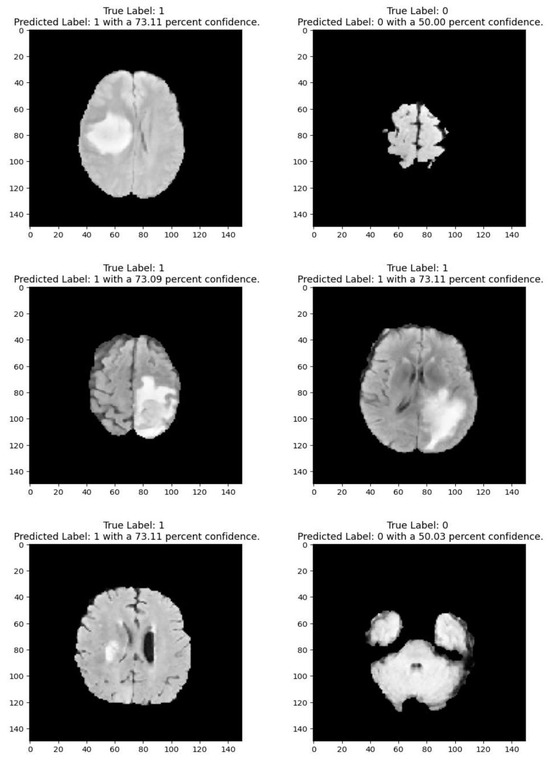

Medical imaging encompasses a diverse array of variations, underscoring the significance of image detection in their interpretation. Our focus was on utilizing MRI scans for the detection of brain tumors. MRI serves as a common modality for both detecting and categorizing brain tumors. In our study, we opted to employ fine-tuned transfer learning models to aid in the identification of brain tumors due to their ability to make precise predictions regarding tumor cells. Figure 9, Figure 10, Figure 11 and Figure 12 display graphical representations of the base model combined with transfer learning operations, and Table 4 presents the corresponding findings. Figure 13, Figure 14, Figure 15 and Figure 16 illustrate the epoch-by-epoch progress of the proposed model, with Table 5 summarizing the associated results. We present a comparison in Table 6 of this study, contrasting the existing research with our proposed approach. Figure 17, Figure 18, Figure 19 and Figure 20 represent the prediction of the model in terms of tumor or non-tumor. The model, named Fine-Tuned Transfer Learning Xception, achieved the highest accuracy of 0.9611, as indicated in the table.

Figure 2 shows that images depicting no tumor typically reveal a serene landscape of brain tissue, characterized by uniform intensity and well-defined anatomical structures. MRI images exhibiting tumors offer a stark contrast. Within these scans, areas of heightened intensity or irregular masses emerge, signaling the presence of pathological growths. These tumors may manifest as distinct lesions, irregular masses, or regions of increased signal intensity, disrupting the otherwise orderly landscape of brain tissue. Notably, the presence of tumors often induces observable changes in adjacent structures, which may appear compressed, displaced, or distorted. By discerning these visual cues, healthcare professionals can effectively differentiate between images with no tumor and those with tumors, facilitating accurate diagnosis and informed treatment decisions for patients